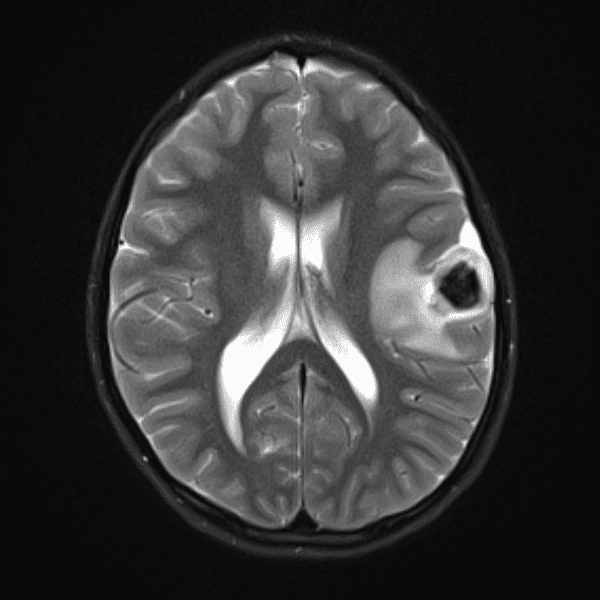

Classic Cases